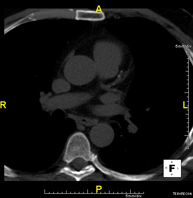

- Tórax- TC Tórax Prueba diagnóstica que consiste en obtener imágenes del tórax de alta definición anatómica (pulmones, corazón, mediastino, grandes vasos, caja torácica, etc.) mediante el empleo de un equipo de TC (Tomografía Computarizada). Dichas imágenes se estudian posteriormente en una estación de trabajo que permite reconstrucciones bidimendionales en diferentes planos del espacio y también reconstrucciones 3D (volumétricas). Algunos estudios requieren el empleo de contraste yodado para mejorar la definición de las imágenes. Prueba diagnóstica que consiste en obtener imágenes del tórax de alta definición anatómica (pulmones, corazón, mediastino, grandes vasos, caja torácica, etc.) mediante el empleo de un equipo de TC (Tomografía Computarizada). Dichas imágenes se estudian posteriormente en una estación de trabajo que permite reconstrucciones bidimendionales en diferentes planos del espacio y también reconstrucciones 3D (volumétricas). Algunos estudios requieren el empleo de contraste yodado para mejorar la definición de las imágenes.

- Angio-TC Aorta torácica Prueba diagnóstica que consiste en el estudio de la aorta torácica (principal arteria del tórax) mediante el empleo de un equipo de TC (Tomografía Computarizada). Esta técnica requiere el empleo de contraste yodado, y proporciona imágenes de alta definición anatómica. El uso del TCMD (TC Multidetector) acorta el tiempo de exploración, disminuye la dosis de radiación y mejora la calidad de la imagen. Gracias a los múltiples detectores, en determinados estudios se puede acoplar la obtención de la imagen con el latido cardíaco, técnica que permite el estudio de la válvula aórtica y de la raíz de la arteria aorta (primeros centímetros), donde el latido del corazón suele provocar múltiples artefactos de movimiento. Prueba diagnóstica que consiste en el estudio de la aorta torácica (principal arteria del tórax) mediante el empleo de un equipo de TC (Tomografía Computarizada). Esta técnica requiere el empleo de contraste yodado, y proporciona imágenes de alta definición anatómica. El uso del TCMD (TC Multidetector) acorta el tiempo de exploración, disminuye la dosis de radiación y mejora la calidad de la imagen. Gracias a los múltiples detectores, en determinados estudios se puede acoplar la obtención de la imagen con el latido cardíaco, técnica que permite el estudio de la válvula aórtica y de la raíz de la arteria aorta (primeros centímetros), donde el latido del corazón suele provocar múltiples artefactos de movimiento.

- Angio-TC Arterias pulmonares (Estudio TEP, Tromboembolismo Pulmonar) Prueba diagnóstica que consiste en el estudio de las arterias pulmonares mediante el empleo de un equipo de TC (Tomografía Computarizada) obteniendo imágenes bi y tridimensionales. En este estudio es imprescindible el uso de contraste yodado, el cual permitirá una mejor definición anatómica. Esta prueba está principalmente indicada en los casos de sospecha de tromboembolismo pulmonar (TEP) para descartar o confirmar la presencia de coágulos sanguíneos en el interior de las arterias. Prueba diagnóstica que consiste en el estudio de las arterias pulmonares mediante el empleo de un equipo de TC (Tomografía Computarizada) obteniendo imágenes bi y tridimensionales. En este estudio es imprescindible el uso de contraste yodado, el cual permitirá una mejor definición anatómica. Esta prueba está principalmente indicada en los casos de sospecha de tromboembolismo pulmonar (TEP) para descartar o confirmar la presencia de coágulos sanguíneos en el interior de las arterias.

- Angio-TC Cardíaco o TC Cardíaco El angio-TC Cardíaco o Coronariografía no invasiva es una prueba diagnóstica que consiste en el estudio de las arterias del corazón o arterias coronarias mediante el empleo de un equipo de TC Multidetector de última generación y de un contraste yodado, obteniendo imágenes bi y tridimensionales. El TC Multidetector o TCMD permite una adquisición de imágenes tan rápida, que se pueden valorar las arterias coronarias con una alta precisión anatómica: estrechamientos o estenosis, calcificaciones, variantes anatómicas, etc., ya que gracias a su rapidez evita el artefacto que provoca el movimiento constante del corazón (tarda menos de diez segundos en adquirir unas 1000 imágenes). La información obtenida precisa de un tratamiento en estaciones de trabajo con programas especializados en la reconstrucción de las arterias coronarias que permiten valorar el número, la localización y las características de las lesiones. Toda esta información se obtiene de manera no invasiva: solo se requiere la punción de una vena periférica (en el brazo). Es necesario que la frecuencia cardíaca no supere los 75 latidos por minuto, por lo que algunos pacientes deberán realizar un tratamiento previo con un fármaco betabloqueante. El angio-TC Cardíaco o Coronariografía no invasiva es una prueba diagnóstica que consiste en el estudio de las arterias del corazón o arterias coronarias mediante el empleo de un equipo de TC Multidetector de última generación y de un contraste yodado, obteniendo imágenes bi y tridimensionales. El TC Multidetector o TCMD permite una adquisición de imágenes tan rápida, que se pueden valorar las arterias coronarias con una alta precisión anatómica: estrechamientos o estenosis, calcificaciones, variantes anatómicas, etc., ya que gracias a su rapidez evita el artefacto que provoca el movimiento constante del corazón (tarda menos de diez segundos en adquirir unas 1000 imágenes). La información obtenida precisa de un tratamiento en estaciones de trabajo con programas especializados en la reconstrucción de las arterias coronarias que permiten valorar el número, la localización y las características de las lesiones. Toda esta información se obtiene de manera no invasiva: solo se requiere la punción de una vena periférica (en el brazo). Es necesario que la frecuencia cardíaca no supere los 75 latidos por minuto, por lo que algunos pacientes deberán realizar un tratamiento previo con un fármaco betabloqueante.